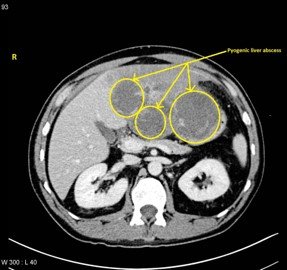

Pyogenic Liver Abscess

–Bacterial infection, often biliary source

–May be multiple lesions

–Thick wall with double target sign

–Gas may be present

–Common in diabetics

–Requires antibiotics ± drainage